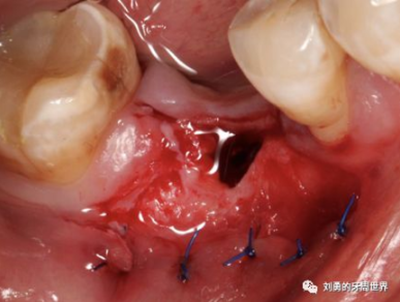

比如下圖:

但是該方法有個(gè)弊端,那就是受區(qū)沒有骨膜了,齦瓣的血供會(huì)變差,有人提出來了改良的方法,就是保留骨膜,但是為了減少骨膜上纖維的移動(dòng)性,對(duì)骨膜進(jìn)行垂直向的全厚層切透,減少骨膜的動(dòng)度,這就是垂直骨開裂的改良方法,如下圖: